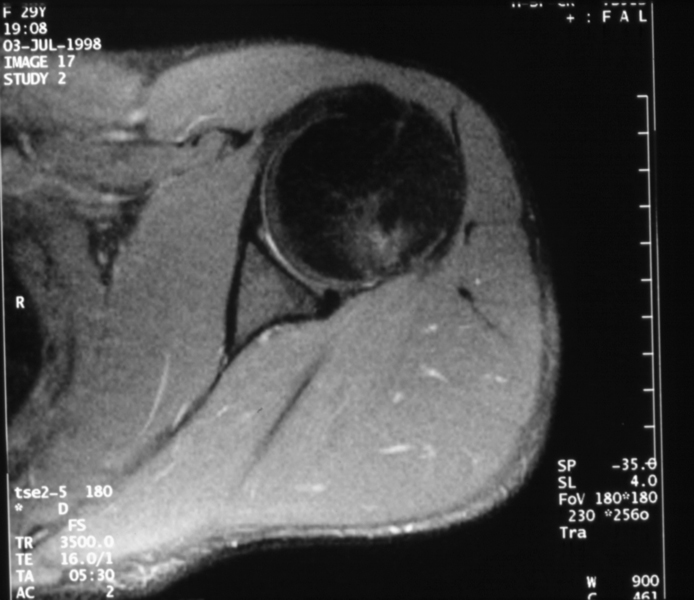

Radiology MS 196 - Normal MR of the Left Shoulder

Identify: Axial - humeral head, glenoid, glenoid labrum, subscapularis muscle, subscapularis tendon, deltoid muscle